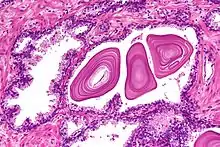

Microanatomy

The prostate consists of glandular and connective tissue.[1] Tall column-shaped cells form the lining (the epithelium) of the glands.[1] These form one layer or may be pseudostratified.[3] The epithelium is highly variable and areas of low cuboidal or flat cells can also be present, with transitional epithelium in the outer regions of the longer ducts.[9] The glands are formed as many follicles, which in drain into canals and subsequently 12–20 main ducts, These in turn drain into the urethra as it passes through the prostate.[3] There are also a small amount of flat cells, which sit next to the basement membranes of glands, and act as stem cells.[1]

The connective tissue of the prostate is made up of fibrous tissue and smooth muscle.[1] The fibrous tissue separates the gland into lobules.[1] It also sits between the glands and is composed of randomly orientated smooth-muscle bundles that are continuous with the bladder.[10]

Over time, thickened secretions called corpora amylacea accumulate in the gland.[1]

Microscopic glands of the prostate

Microscopic glands of the prostate